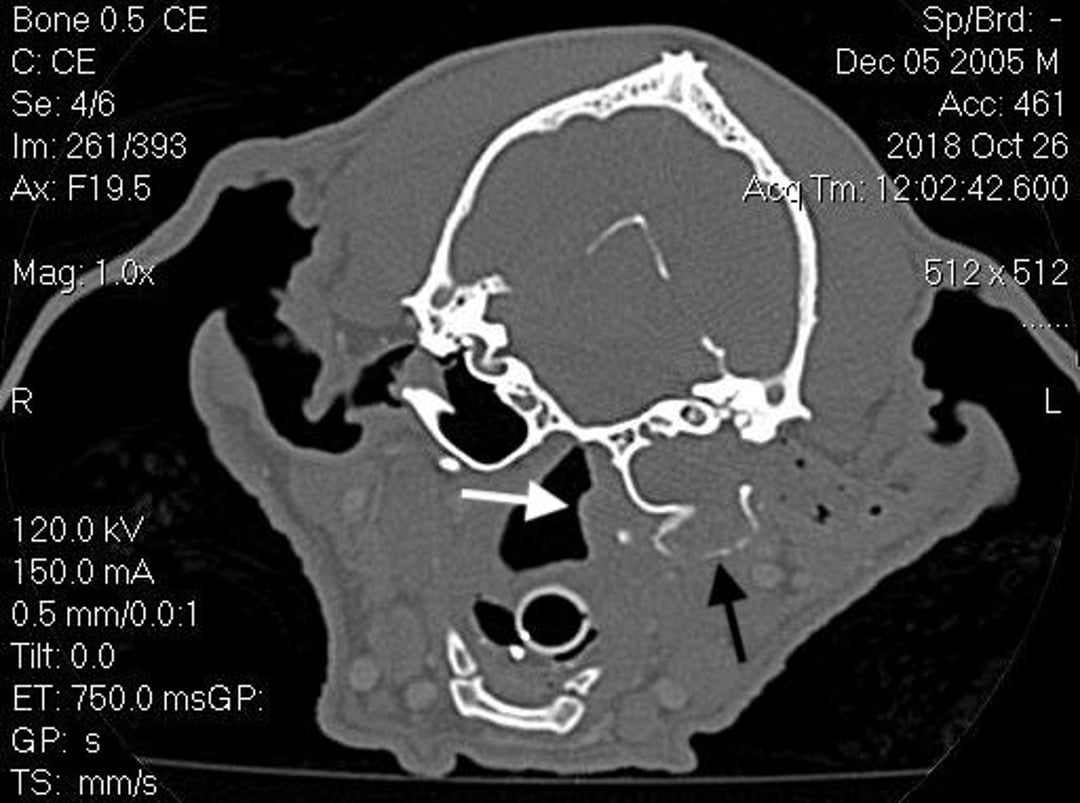

El diagnóstico implica imágenes avanzadas para evaluar los cambios en el oído medio. Las radiografías de la bulla timpánica se pueden realizar si no se dispone de TC o RM, pero no proporcionan tanta información. Los colesteatomas causan lisis, esclerosis y proliferación de la bulla. La bulla también puede expandirse y llenarse de tejido blando. La otitis externa también puede ser evidente. Las muestras para citología e histología deben enviarse cuando sea posible para confirmar el tipo de lesión presente. El cultivo del oído medio o externo también debe considerarse basándose en la citología debido a la posibilidad de infección secundaria.